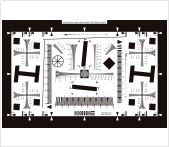

| FDA認證-分辨力 | ISO 12233 |  | FDA認證 | 清晰度測試 | |